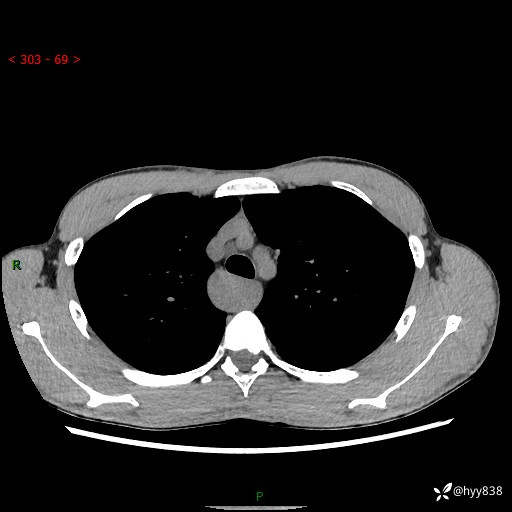

年轻男性,发现后纵隔占位1周余。征象简单,难在定位---结果公布~

现病史:患者于1周前体检行检查发现后纵隔占位,患者平素无明显咳嗽咳痰,无心慌、胸闷、胸痛、呼吸困难、低热、盗汗,无头痛、头晕,无腹痛、腹胀等不适。现患者欲求进一步治疗,遂来我院就诊,以“纵隔占位”收入我科。 患者自起病以来,精神可,睡眠可,饮食可,大小便正常,体重无明显改变。

胸部CT平扫+增强